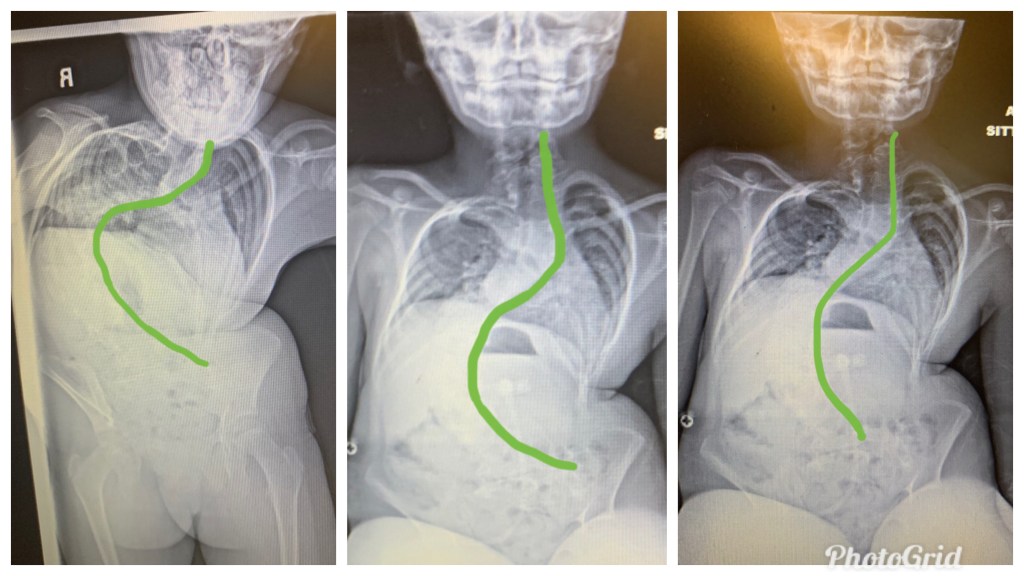

Scoliosis is an abnormal side to side “S”- or “C”-shaped curvature of the spine.

According to the Scottish Rite for Children, confirmation of a diagnosis for scoliosis by taking an x-ray. The most compelling evidence is a Cobb angle (degree of curvature) > ten degrees.